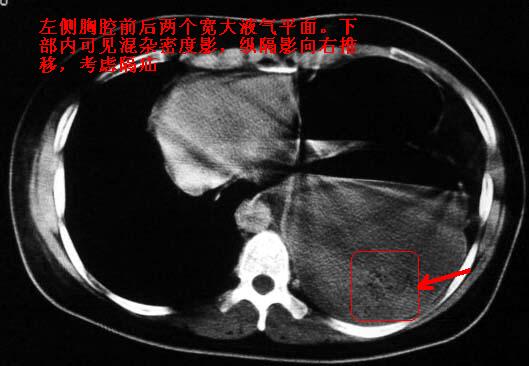

标题: CT5517:女性、24岁,反复胸痛、气促不能平卧半月。

左侧气液腔与胃腔影相连,考虑膈疝。钡餐检查有助于诊断。

我看这是膈疝,在纵隔窗第六\\七幅图像上可见胃粘膜影,再者可见两个腔影,这在液气胸是不会有的.

支持膈疝,纵隔窗内可见消化道的内容物。

液气胸 怎么会有2 个大腔?

还是个膈疝